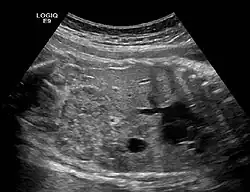

Ectopic crossed fused kidney in a fetus approx. 34 weeks